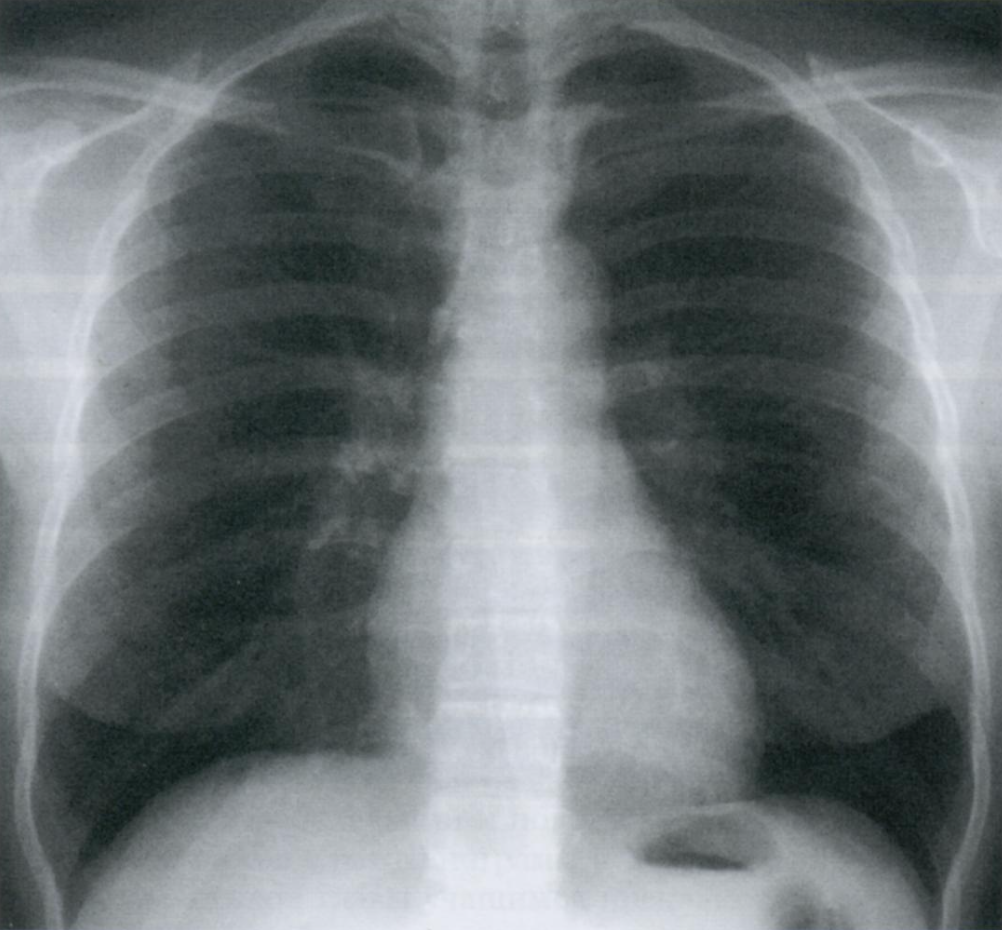

Обратите внимание на верхушки легких. Что Вы ещё видите на снимке?

Обычно Rx выполняются при глубоком вдохе, когда в легком находится максимально возможное количество воздуха, и потому оно имеет наименьшую плотность. При корректно выполненом снимке на вдохе должны считаться 10 ребер по задней поверхности (или шесть по передней).

Задние сегменты ребер расположены горизонтально, передние проходят косо кпереди и книзу.

Верхушки легких, которые прикрыты первым ребром, могут выглядеть как участки сверхпрозрачности. Это обман зрения от перепада контрастности между ребром и верхушкой легкого.

Не перепутайте с буллой/пневмотораксом.

Rx грудной клетки на вдохе с признаками левостороннего пневмоторакса.

Normalmente las radiografías se toman en inspiración profunda, de manera que el pulmón tiene la mayor cantidad de aire posible y por tanto la menor densidad. En una placa correctamente inspirada deben poder contarse 10 costillas por su parte posterior (o seis por la anterior).